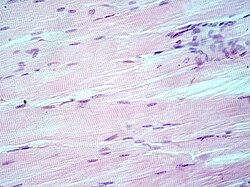

Hrskavica: stanične jezgre (plavoljubičaste), izvanstanični materijal (ružičast). Neinvanzivni tumor u tkivu dojke manji od 1 mm, stanične jezgre (plavoljubičaste), izvanstanični materijal (ružičast). Plućno tkivo uzeto bolesniku s emfizemom (kronična opstruktivna plućna bolest). Jezgre stanica (plavoljubičasto), crvene krvne stanice (jarko crvene), ostala stanična tijela i izvanstanični materijal (ružičasti) i zračni prostori (bijeli). Mišićno tkivo: stanične jezgre (plavoljubičasto), citoplazma i izvanstanični materijal (ružičasto).